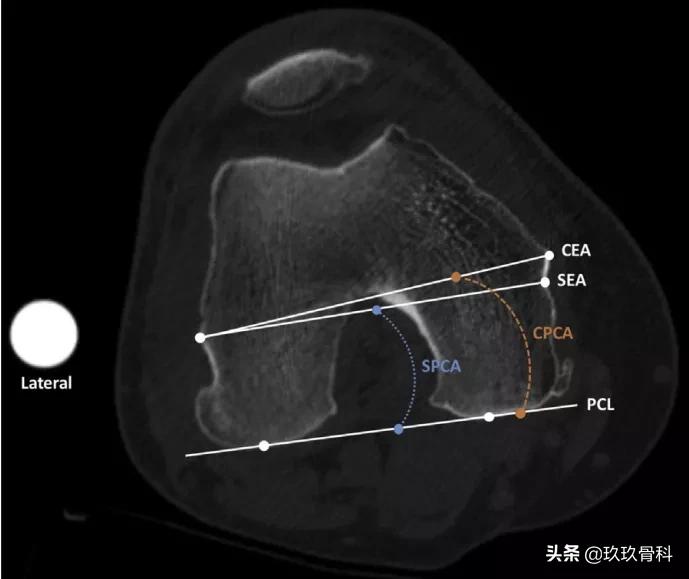

外科和临床后髁角。外科后髁角(sPCA)是指连接股骨内外髁最后关节面间的后髁线(PCL)与连接股骨外上髁到内侧骨凸槽间的外科通髁线间(SEA)的夹角。临床后髁角(cPCA)是指PCL与连接股骨内外上髁间的临床通髁线间(CEA)的夹角。